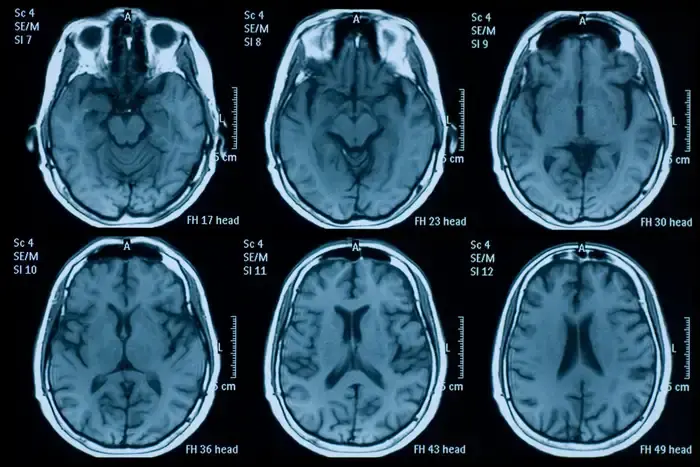

Pesquisadores da Universidade de Nottingham analisaram exames cerebrais de quase mil pessoas antes e depois da pandemia e constataram que, em média, os cérebros envelheceram 5,5 meses a mais do que o esperado no período.

As alterações ocorreram tanto na substância cinzenta — ligada à memória e ao raciocínio — quanto na substância branca, responsável pela comunicação entre regiões cerebrais.